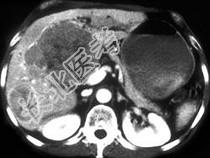

- 单项选择题女,67岁, 右上腹疼痛,消瘦四月余, CT检查如图,最可能的诊断为 ( )

A、肝囊肿

B、肝癌

C、肝脓肿

D、肝血管瘤

E、肝转移瘤